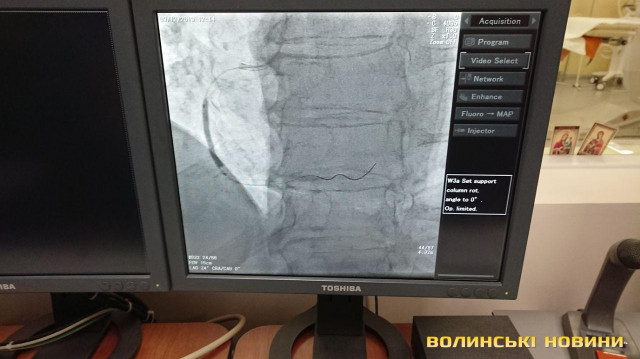

З 2013-го року реперфузійні центри працюють за системою «24/7», тобто ми допомогу надаємо у будь-який час і кожного дня. З 2018 року до цієї роботи долучився реперфузійний центр у м. Ковель завдяки ангіографу, встановленому за кошти субпроекту Світового банку. У нашому центрі щодня маємо 3-5 процедур. Також почали проводити тромбоекстракцію у пацієнтів з ішемічним інсультом. Це складна процедура, яку роблять у небагатьох клініках України. Суть у тому, що при інсульті треба вчасно відкрити судинку. У судину заводиться спеціальне обладнання і проводяться маніпуляції із видалення тромбу. Є випадки, що молодим людям ставало значно краще.